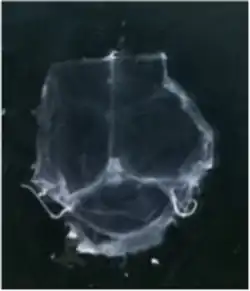

To visualize the dura mater using immunohistochemistry, the dura must first be fixed within the skullcap. It is prepared by cutting around the base of the skull (inferior to the post-tympanic hook) and removing the lower portion of the skull and brain. Following fixation, the dura can be dissected out of the skullcap as a single piece of tissue that can be utilized for histological analysis.[12]

Although several studies proposed the existence of lymphatic vessels in the dura mater, the presence of the meningeal lymphatic system was accepted in 2015, when two independent studies published by Louveau et al.[1] and Aspelund et al.[2] provided convincing data using novel methods. Louveau et al. noticed an unusual alignment of immune cells along the dural sinus using a meningeal whole-mount technique. Using lymphatic endothelial cell-specific markers and electron microscopy, the authors found that the immune cells were not inside blood vessels, but rather were organized inside lymphatic vessels within the meninges, a system of membranes that envelop the brain and spinal cord.[1]